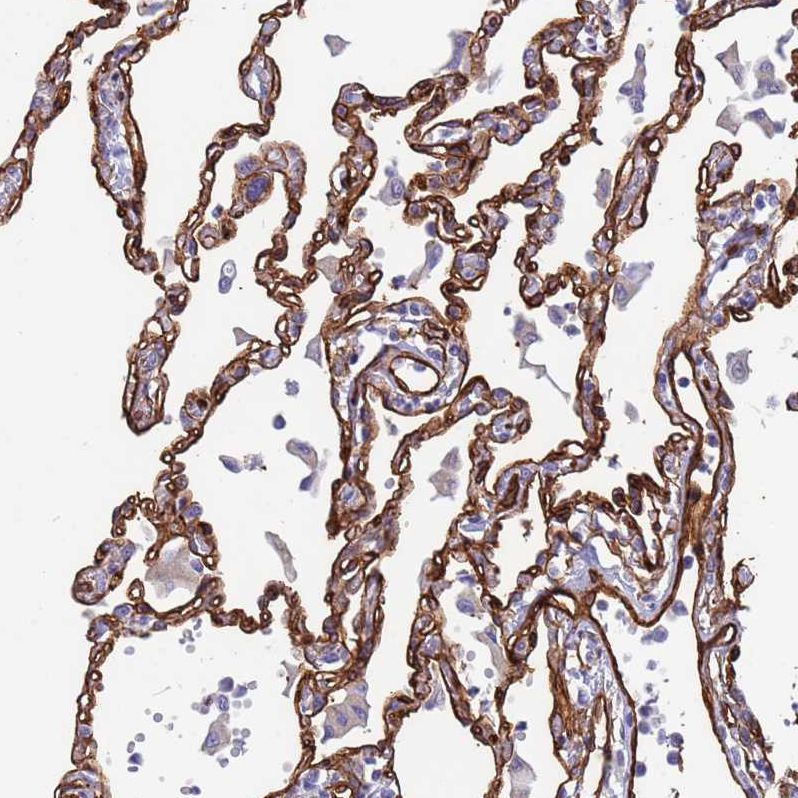

Immunohistochemical staining of human Breast shows strong membranous positivity in adipocytes.